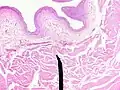

Microanatomy

When viewed under a microscope, the bladder can be seen to have an inner lining (called epithelium), three layers of muscle fibres, and an outer adventitia.[8]

The inner wall of the bladder is called urothelium, a type of transitional epithelium formed by three to six layers of cells; the cells may become more cuboidal or flatter depending on whether the bladder is empty or full.[8] Additionally, these are lined with a mucous membrane consisting of a surface glycocalyx that protects the cells beneath it from urine.[14] The epithelium lies on a thin basement membrane, and a lamina propria.[8] The mucosal lining also offers a urothelial barrier against the passing of infections.[15]

These layers are surrounded by three layers of muscle fibres arranged as an inner layer of fibres orientated longitudinally, a middle layer of circular fibres, and an outermost layer of longitudinal fibres; these form the detrusor muscle, which can be seen with the naked eye.[8]

The outside of the bladder is protected by a serous membrane called adventitia.[8][16]

Vertical section of bladder wall- Layers of the bladder wall and cross-section of the detrusor muscle

Anatomy of the male bladder, showing transitional epithelium and part of the wall in a histological cut-out